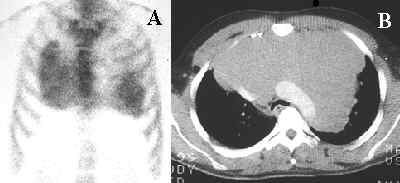

Malignant Pleural EffusionMalignant pleural effusion

The bone scintigram (A) shows diffuse accumulation of the radiotracer in a malignant pleural effusion within the right hemithorax of this patient with lung carcinoma. A CT scan (B) confirms the presence of a right-sided pleural effusion.